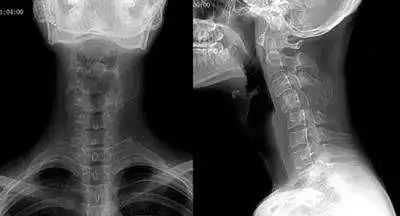

虽然当人体在端坐或站立时,从侧面视察可见颈部似乎是直的,但其实包绕于内的颈椎并不是直的,而是在其中段有一向前凸出的生理弧度,我们把这一向前的弧形凸起称为颈椎的生理弯曲。我们通过X线片检查可见:在各个颈椎椎体后缘都有形成的连续、光滑的弧形曲线,称之为颈椎弯曲。颈椎生理弯曲的存在能增加颈椎的弹性,减轻和缓冲震荡,防止外力对脊髓和大脑的损伤。

长时间不正确的久坐、或是劳累、颈椎缺少活动、脊柱损伤、脊柱钙化等就会导致颈椎生理弯曲变直。颈椎的前凸可逐渐消失,甚至可变直或呈反张弯曲,即向后凸,成为颈椎病在X片上重要的诊断依据之一。